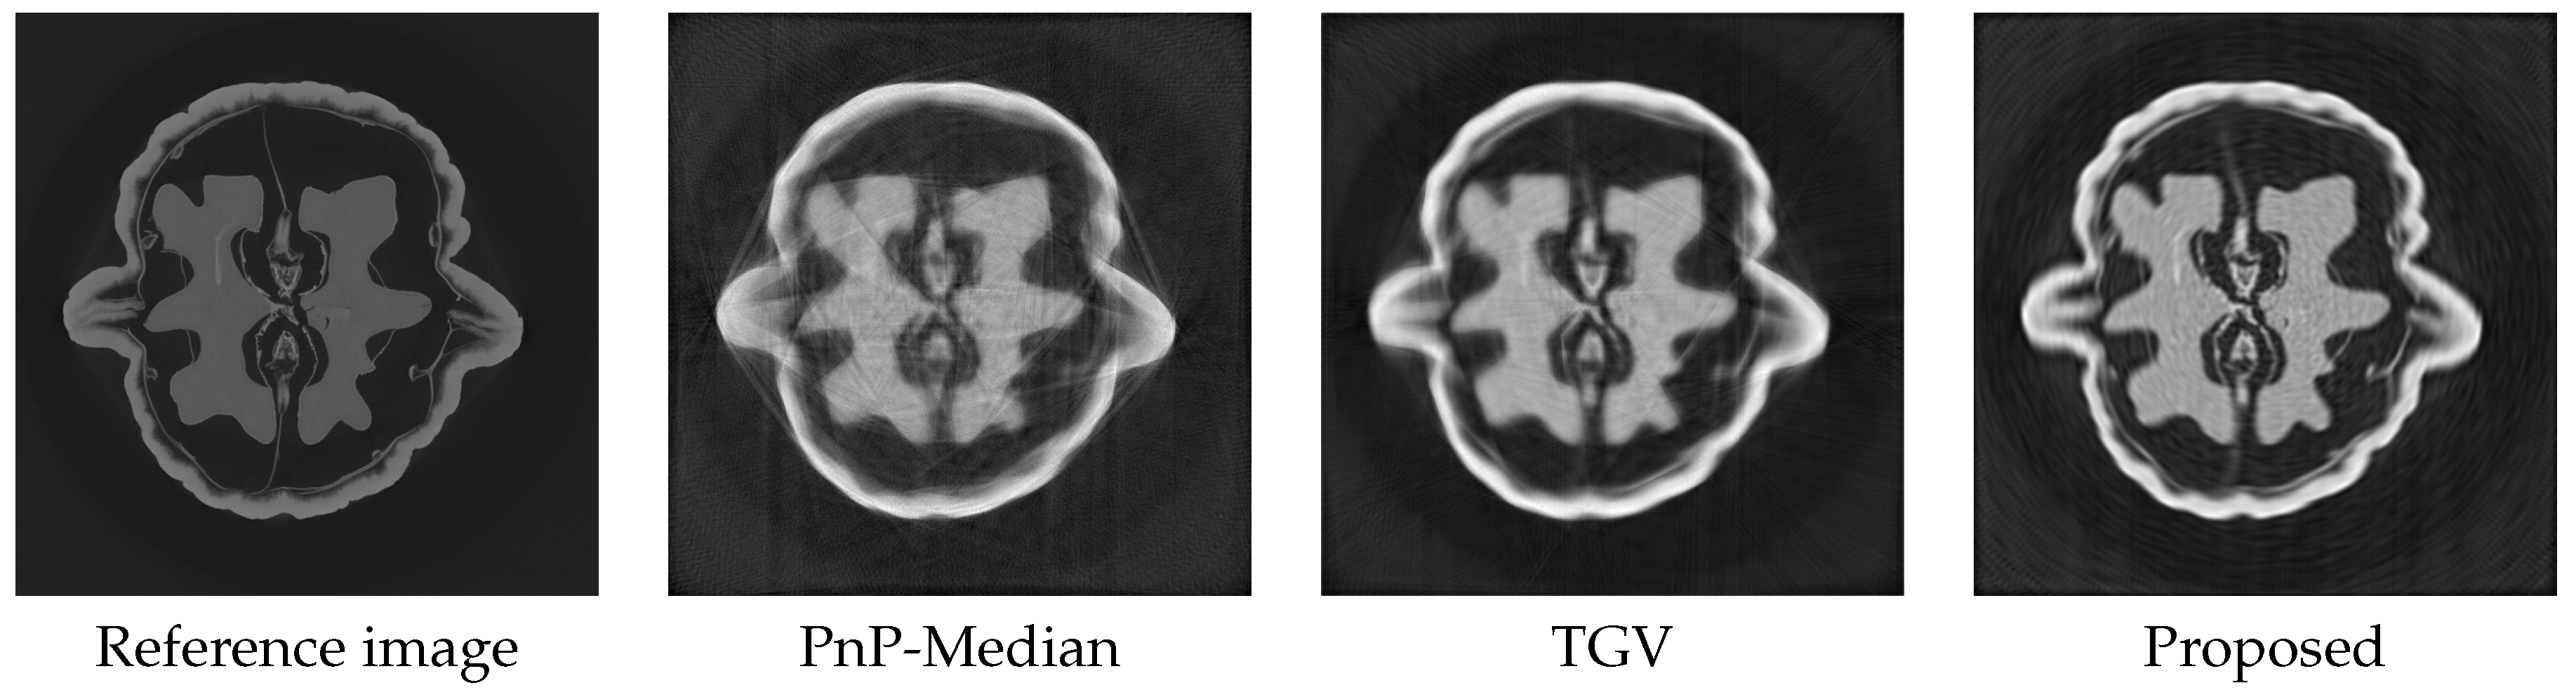

4.3. Experimental Results